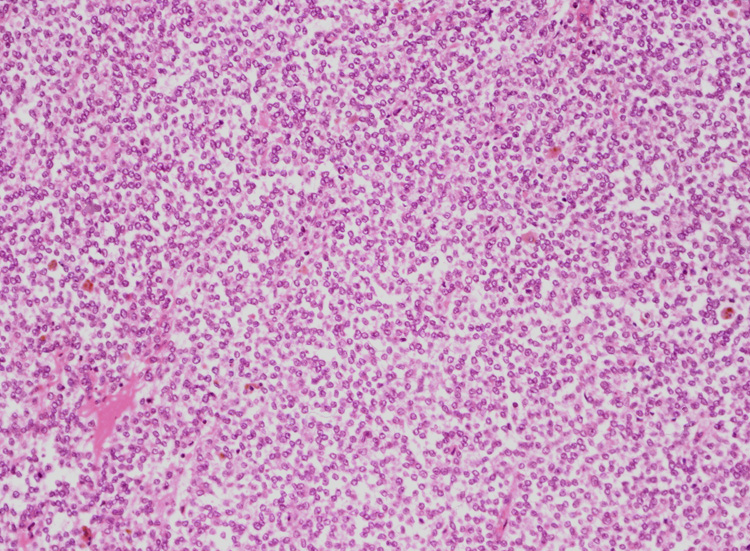

腫瘍細胞はシート状密に増殖する、類円形小型淡明な核をもった細胞質の乏しい細胞からなる。細胞分裂像は目立たなかった。(Fig.05,06), 線維間質部分の拡大所見。腫瘍細胞が小さな集簇をつくって浸潤している。(Fig.07) Fig08では血管周囲性ロゼットが認められる。